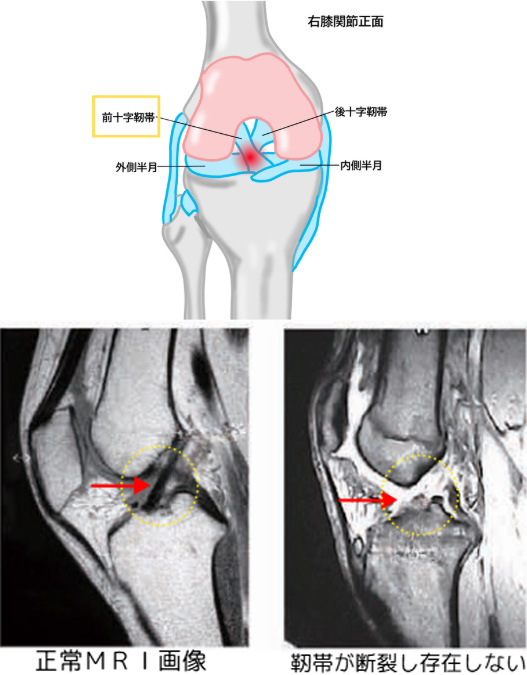

前十字靭帯損傷(ACL損傷)

概要

膝の中にある前十字靭帯(ACL)は、すねの骨(脛骨)が前方にずれるのを防ぎ、膝の回旋(ねじれ)を制御する役割を持つ重要な靭帯です。

ジャンプの着地や急な方向転換、接触プレーなどで損傷しやすく、特にサッカー・バスケットボール・スキーなどのスポーツ中に多く発生します。

治療方法

治療方針は年齢やスポーツレベル、日常生活での膝の使い方によって異なります。スポーツ復帰を希望する方や膝の不安定感が強い場合は、靭帯を再建する手術が必要になることが多く、手術前後のリハビリも重要です。

一方で、スポーツを行っていない方や膝の不安定性が少ない方は保存療法によって機能改善を図る場合もあります。ただし長期的には半月板損傷や軟骨損傷を引き起こしやすく、変形性膝関節症のリスクが高まることが知られています。将来の膝の健康を守るためにも、治療方針は慎重に検討する必要があります。